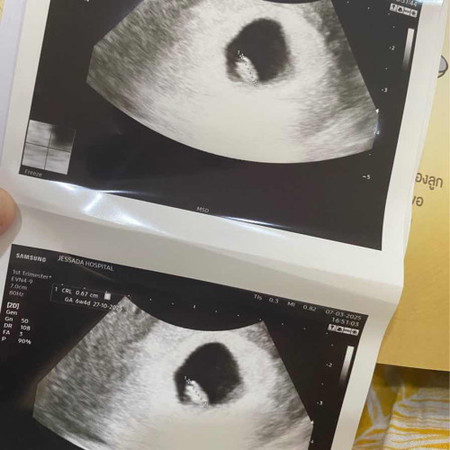

ถุงไข่แดง 6วีค

6วีค คุณหมอบอกว่าถุงไข่แดงเล็กนิดเดียว นัดอีก2วีคหน้ามาดูใหม่ มีใครเคยเจอแบบนี้บ้างไหมคะ กลัวว่าเจ้าจิ๋วจะไม่เติบโตค่ะ🥲